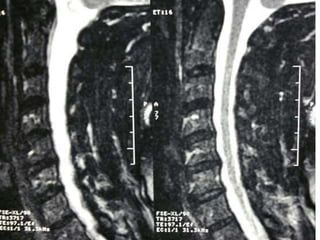

77 year old woman with h/o hand weakness/numbness/ataxia

Prior acdf 14 years ago

Note:the black line directly posterior to the vertebral bodies and relative

Thinning of spinal cord, note normal disc height